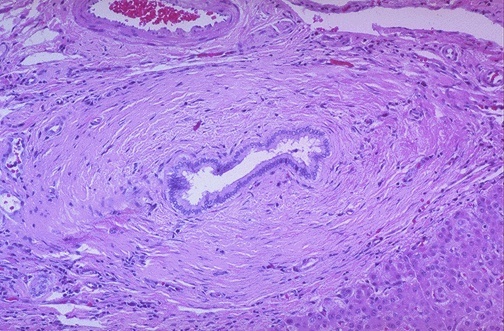

Primary sclerosing cholangitis:

showing onion skin fibrosis of bile duct

Stong Assoc. with Ulcerative Colitis. P-ANCA

increased IgM. incr risk of cholangiocarcinoma